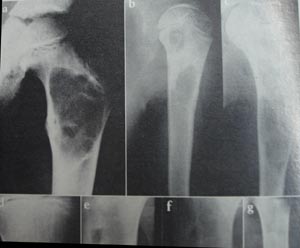

View Osteoclastoma

Osteoclastoma